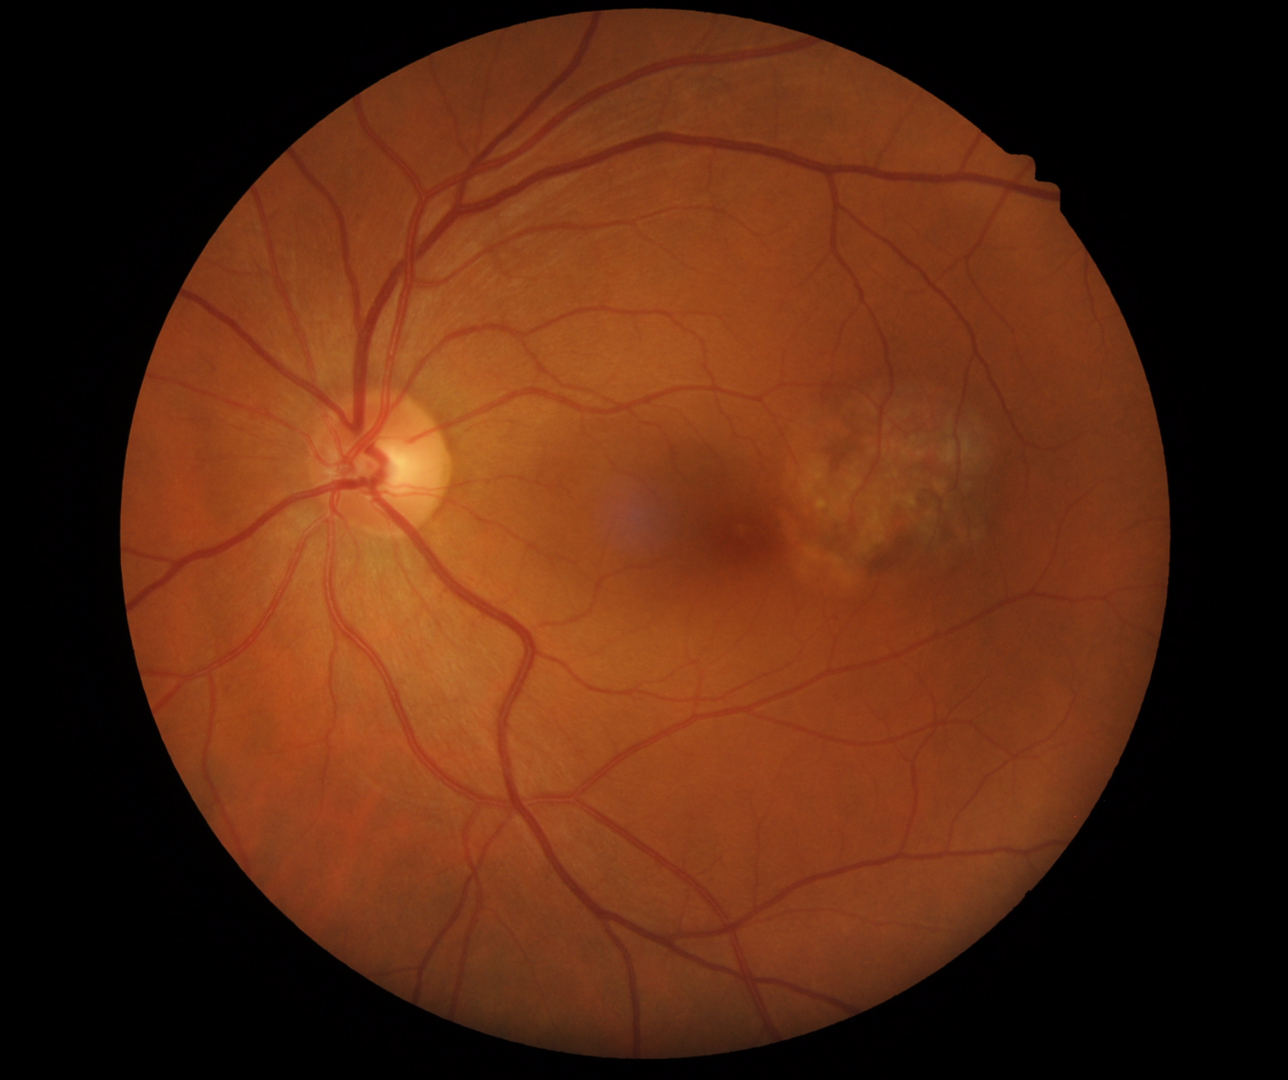

A 47 year old Caucasian female with best corrected visual acuity of 6/6- (20/20-) in the left eye. Testing with an Amsler grid shows infero-nasal distortion.

Torpedo maculopathy is unilateral, hypo-pigmented lesion of the RPE that is round in shape with a tip that points towards the central macula (“torpedo” shaped). The lesions are located temporal to the fovea.

There are two type of torpedo maculopathy – the first which show attenuation of the outer retina only, and the second (type 2) which shows this attenuation of the retinal layers plus outer retinal cavitation with a detachment of the neurosensory retina.